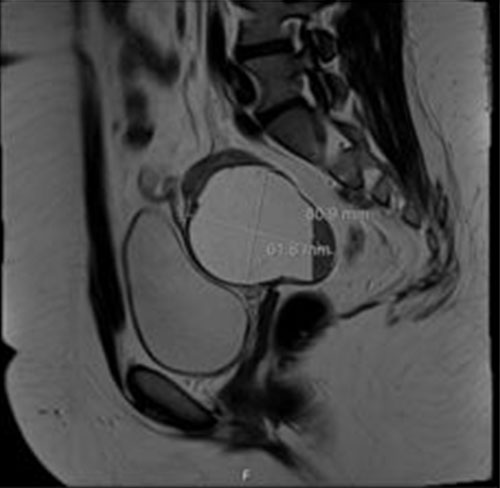

A pelvic ultrasound demonstrated normal arterial and venous flow and waveform to the left ovary. Right ovary was surgically absent. As shown in Figure 3, a complex 5.9 × 6.8 × 6.29 cm left adnexal/pelvic cul-de-sac cyst was seen which demonstrated mobile low-level echoes and an echogenic, avascular solid component peripherally. Further imaging was obtained. Magnetic resonance imaging (MRI) of the abdomen and pelvis showed an 8 cm left adnexal cystic mass favored to represent large hematosalpinx (Figure 4), with slight thickening of the right uterosacral ligament which may be related to endometriosis.

Figure 3: Transvaginal ultrasound imaging with a left adnexal mass measuring 5.94 × 6.80 × 6.29 cm (Case 2).

Figure 4: MRI imaging showing 8.09 × 6.18 cm left adnexal mass, favoring hematosalpinx (Case 2).